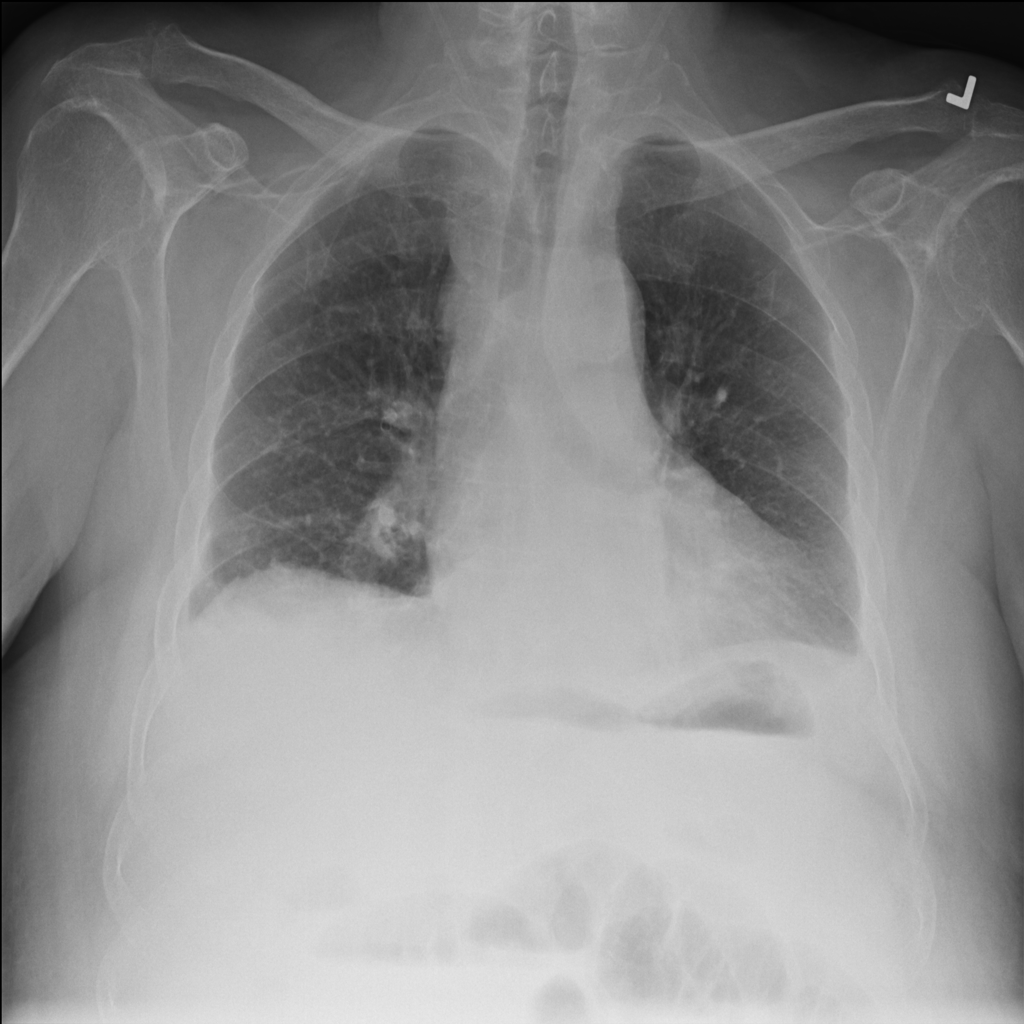

We conclude our analysis with consideration of the ChestXray-14 [RIZ+17] dataset. This dataset contains frontal X-ray images labeled with 14 different conditions. ChestXray-14 is a multi-label tagging task (i.e., a single image can have more than one condition), so we treat each condition as its own binary problem. In this section, we focus on the condition Effusion. Results on other conditions can be found in Appendix C.3.

The trained SVM identifies visually distinguishable failure mode directions in latent space. As shown in Figure 11, the representative images flagged by this SVM as most incorrect are blurrier and less bright. Moreover, this trend is not reflected by the least confident images, indicating that our framework is isolating a different trend than the one corresponding to ordering the images by base model confidence.

In fact, we find that the SVM may be picking up on the position in which the exam was conducted. While the majority of the X-rays are Posterior-Anterior (PA) radiographs, a little over a third are Anterior-Posterior (AP). PA radiographs are usually clearer, but require the patient to be well enough to stand [TB20]. Examples of AP and PA radiographs from the dataset can be found in Appendix C.3.

As shown in Table 13, the SVM for the class “no effusion” flags a large number of the AP radiographs as incorrect. This indicates that the model might indeed rely on the position in which the radiograph was taken to predict whether the patient was healthy. Moreover, the SVM selects the AP examples more consistently than ordering the radiographs by the base model’s confidence (Figure 13).